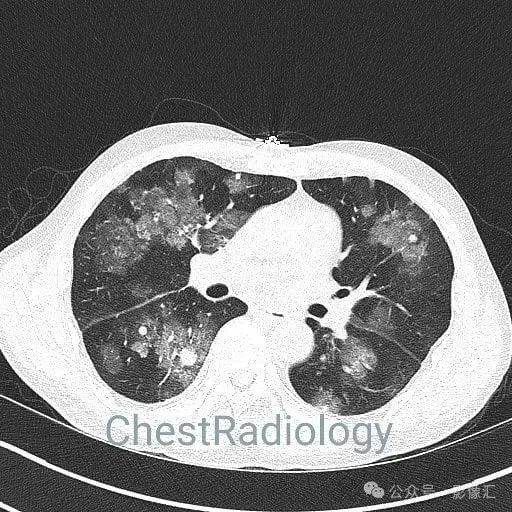

咯血患者,肺部弥漫磨玻璃,细节决定成败?

成年男性,咯血,细节决定成败,你看到了吗?欢迎评论区留言